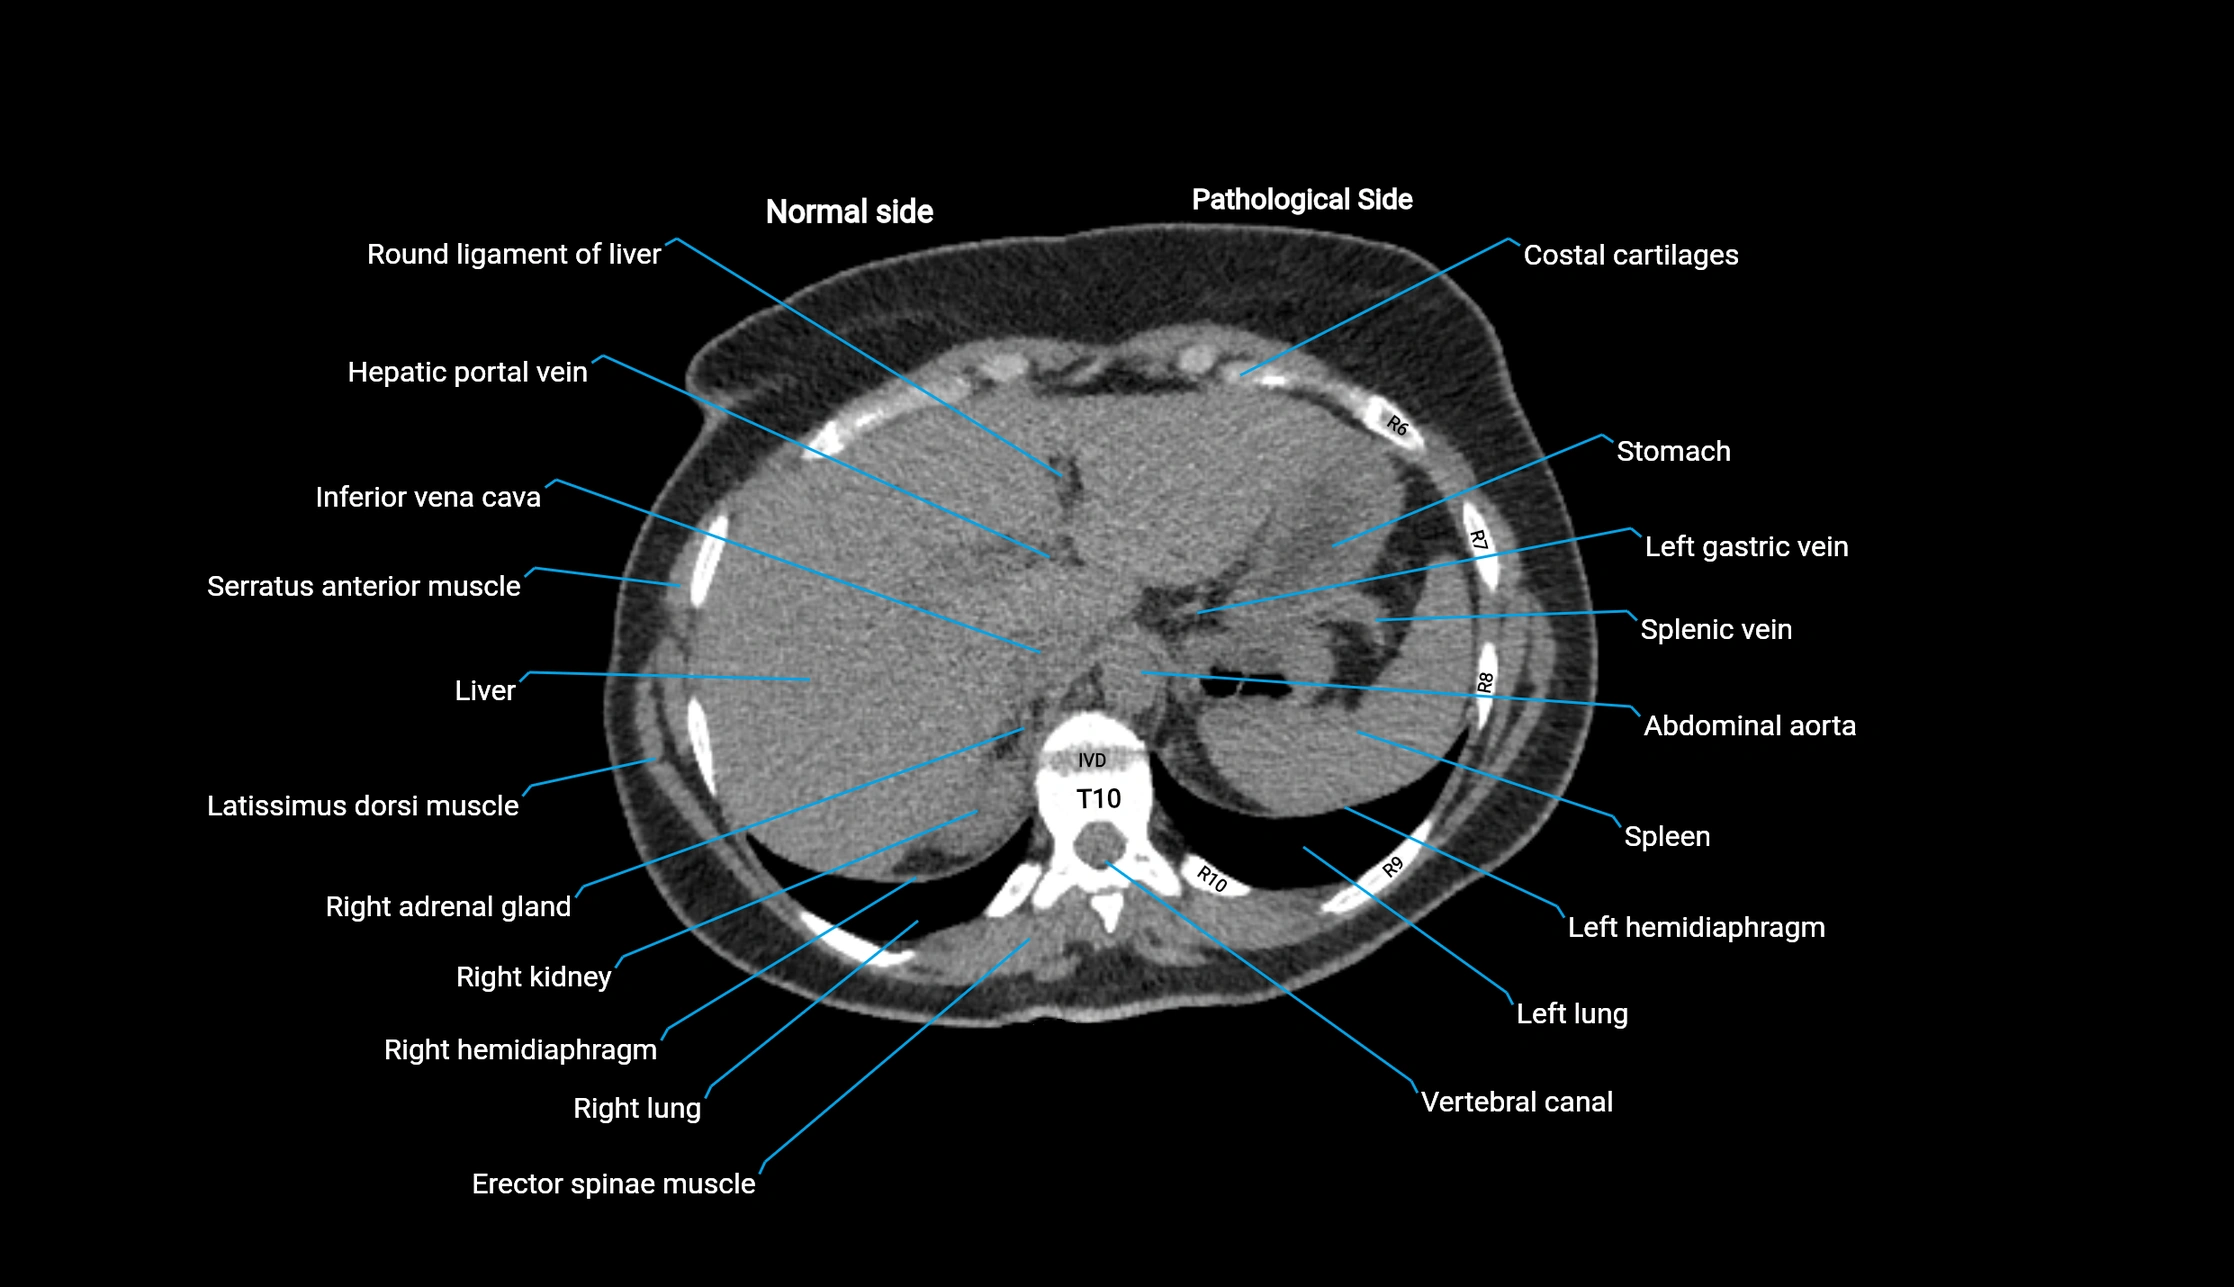

CT image

image